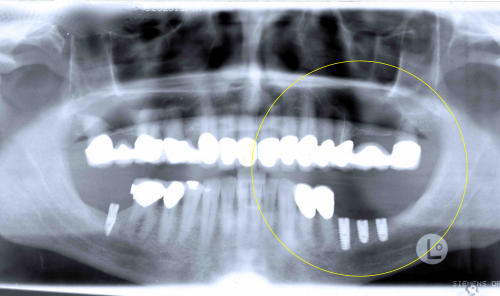

Situation vorher (Brückenanhänger,

abnehmbar mit Geschiebe, ist bereits

entfernt)